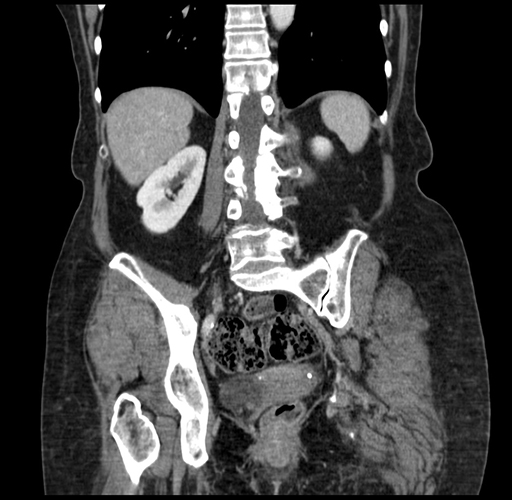

Pre-Chemo: Coronal Venous

Coronal Venous